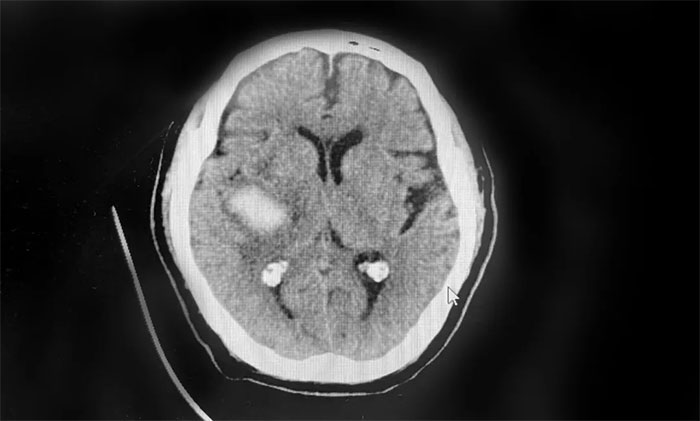

跌倒,是老年人意外致死致殘的重要原因。除了造成骨折,慢性硬膜下血腫(CSDH)是老年人跌倒后常見(jiàn)的中樞神經(jīng)系統(tǒng)疾病,嚴(yán)重威脅患者生命健康。...【詳細(xì)】